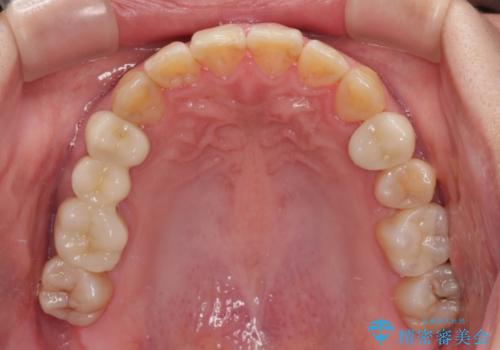

- 奥歯に問題が多くて困っているとのことで来院された患者様です。

開咬により奥歯のみが接触している状態で、前歯部にほとんど接触のない状態で、奥歯に非常に負担のかかる咬み合わせでした。

また、欠損や根管治療の必要な歯など、むし歯による問題も多く散見されました。

まずはむし歯の治療を行い、その後ワイヤー矯正にて咬み合わせを改善し、途中インプラント埋入を行い、矯正治療後に補綴治療を行うこととしました。